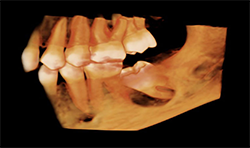

Case 1: 12-year-old boy with delayed eruption of the mandibular left second molar

The panoramic radiograph (Fig. 1) shows a well-defined, corticated, radiolucent area mesial to the mandibular left second molar. The inferior alveolar nerve canal is displaced inferiorly.

CBCT images of the same patient (Figs. 2A, 2B, 2C) reveal the lesion extends mesial to the third molar follicle, displacing the thinning buccal cortex. The lesion arises from the cementoenamel junction (CEJ) of the second molar. The inferior alveolar nerve canal is intact. The lesion was treated by surgical removal and submitted for histological examination. The histopathologic diagnosis was a dentigerous cyst.